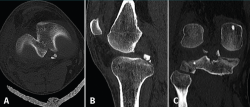

Figure 4. Arthroscopy views from the anterolateral portal, showing bone avulsion with a fragment of the medial root (A), suture advancement through the meniscal root (B), and bone avulsion reduced in its bone bed (C).

Arthroscopy confirmed the diagnosis by visualizing the avulsed root and bone fragment at medial level (Figure 4A) and the radial lesion of the external root (Figure 5). Palpation of both roots evidenced clear instability. The ACL was greatly affected, with subtotal rupture, while the PCL presented correct stability in response to palpation and testing.

Figure 5. Arthroscopic view from the anterolateral portal, identifying the radial lesion of the root of the external meniscus.

The medial root avulsion fracture was repaired using a standard transtibial pullout technique(1,3,6). Suturing required the use of no. 2 FiberWire® (Arthrex, Naples, FL, USA ) through the root with the Knee Scorpion™ system (Arthrex, Naples, FL, USA) (Figure 4B). A FlipCutter® III retrograde reamer (Arthrex, Naples, FL, USA) with a Unicorn Meniscal Root (UMR) guide (Arthrex, Naples, FL, USA) was used to drill a blind tibial tunnel, 6 mm in diameter and 15 mm in length, from the bone bed of the medial meniscus towards the anteromedial tibial cortical layer. The meniscus sutures were retrieved through the trans-bone tunnel with a FiberStick® (Arthex, Naples, FL, USA). The suture was knotted through a metal button, securing correct reduction of the meniscal avulsion (Figure 4C).

The rupture of the lateral meniscal root was repaired with two U-shaped meniscal sutures using a Knee Scorpion™ suture passer. Lastly, reconstruction of the ACL was carried out with an anterior tibial tendon allograft with proximal and distal cortical suspension fixation according to the all-inside technique, avoiding the coalition of tunnels at tibial medial level.